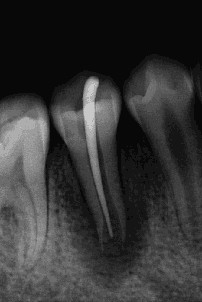

术后1